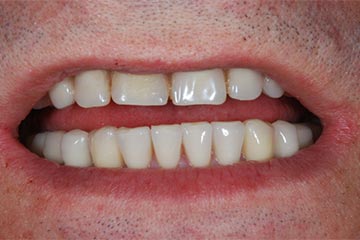

Con protesi fissa superiore e protesi fissa inferiore

I denti irrecuperabili dell'arcata superiore ed inferiore del paziente di anni 65

sono stati sostituiti da 10 impianti, cioè protesi radicolari endo-ossee che sostengono le protesi fisse superiore ed inferiore.